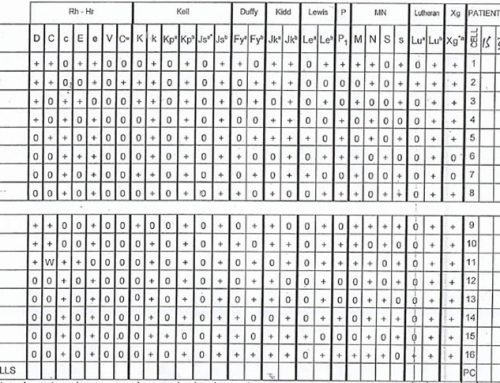

Lupus anticoagulant, anti-B2 glycoprotein, anti-cardiolipin antibodies absent

Factor V Leiden homozygous normal

Jak2 V617F not detected

PNH screen negative

Homocysteine normal

Anti-thrombin III 121%

Protein C 106%

Protein S 10%